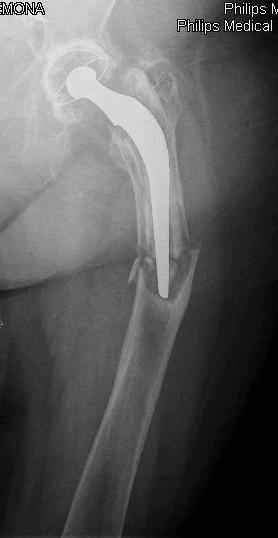

You transformed a cemented hip prosthesis to a cementless revision hip prosthesis with a little approach.

* your nail has a point of minus resistance at the tip of femural stem and at the fulcrum of the fracture; by the time could it break?

* by the time stem and nail could reciprocally move?

* distal fixation of the nail is based near only on two screws : are they sufficient to secure a good stability before fracture consolidation?

I generally should prefer a long stem revision prosthesis, as that allegated.

The nail tip is jammed. Since it is conical, it can only be jammed more with axial load.

I'd say yes because we use same 6 mm screws for femoral nailing and allow immediate weight-bearing regardless of fracture pattern.